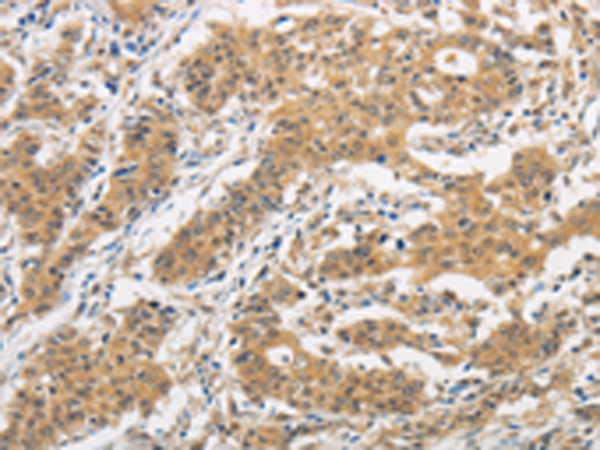

分类: 科研抗体货号: P00473别名: ICSBP; IRF-8; ICSBP1; IMD32A; IMD32B; H-ICSBP应用: IHC反应种属: Human, Mouse